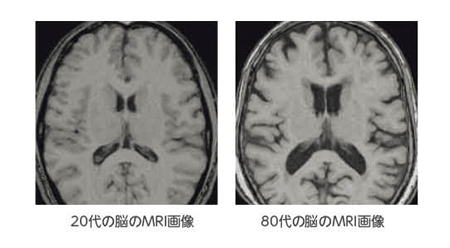

高齢者に多い「慢性硬膜下血腫」

慢性硬膜下血腫は、高齢者に特に多い病気です。転倒して頭をぶつけてから数週間〜数か月後に、ゆっくり症状が出てきます。「転んだのは覚えているけど大したことはなかった」「頭は打ったけど病院には行かなかった」というケースでも発症することがあります。

慢性硬膜下血腫の怖いところは、症状がゆっくり進むことです。これは、軽い頭部打撲(転倒など)をきっかけに、脳と頭蓋骨の間に血液がゆっくり溜まっていくのが原因で、頭を打った時から時間が経過して発症することがあります。本人はもちろん、周囲の家族等が日常の変化に注意を払うことも重要となります。